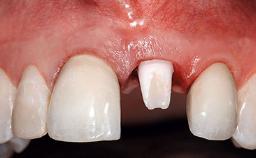

A 49-year-old female patient was referred for implant therapy to replace the upper right central incisor (tooth 11). The tooth had been assessed by an endodontist who diagnosed a vertical fracture of the root. The tooth had a hopeless prognosis and needed to be extracted. The patient was healthy and was not taking any medications. She was allergic to penicillin. The patient had high esthetic demands but her expectations were realistic. The extraoral examination revealed no facial asymmetries. The right temporomandibular joint demonstrated an opening click but was otherwise asymptomatic. The lip line was high with a significant gingival display.

Patient's Esthetic Expectations Low Medium High

Lip Line No exposure of papillae Exposure of papillae Full exposure of mucosa margin